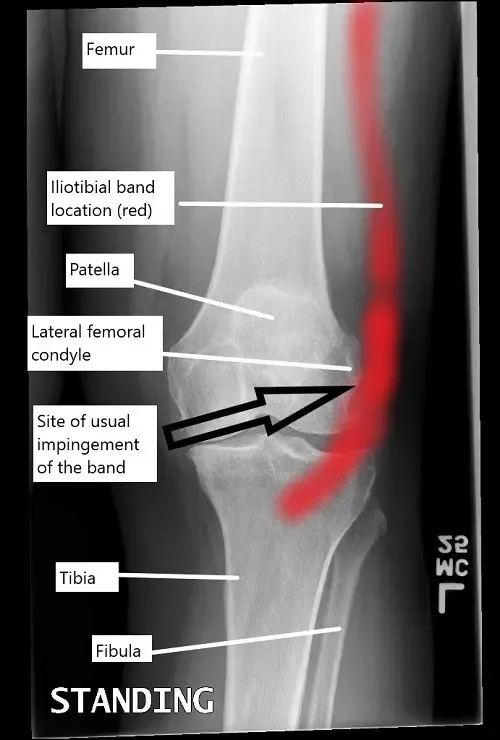

Una radiografía de rodilla que ilustra la ubicación de la banda iliotibial y el lugar habitual del pinzamiento.

La banda iliotibial es una banda fibrosa que recorre el lado externo del muslo, desde la cadera hasta la espinilla. Conecta los músculos tensor de la fascia lata y glúteo mayor con la tibia. La banda tibial ayuda a estabilizar la rodilla durante actividades como caminar, correr y montar en bicicleta. Normalmente, la banda tibial se mueve suavemente sobre el cóndilo femoral lateral a medida que la rodilla se dobla y se endereza. Sin embargo, cuando la banda tibial se vuelve tensa o irritada, puede rozar contra el cóndilo femoral, provocando inflamación y dolor.